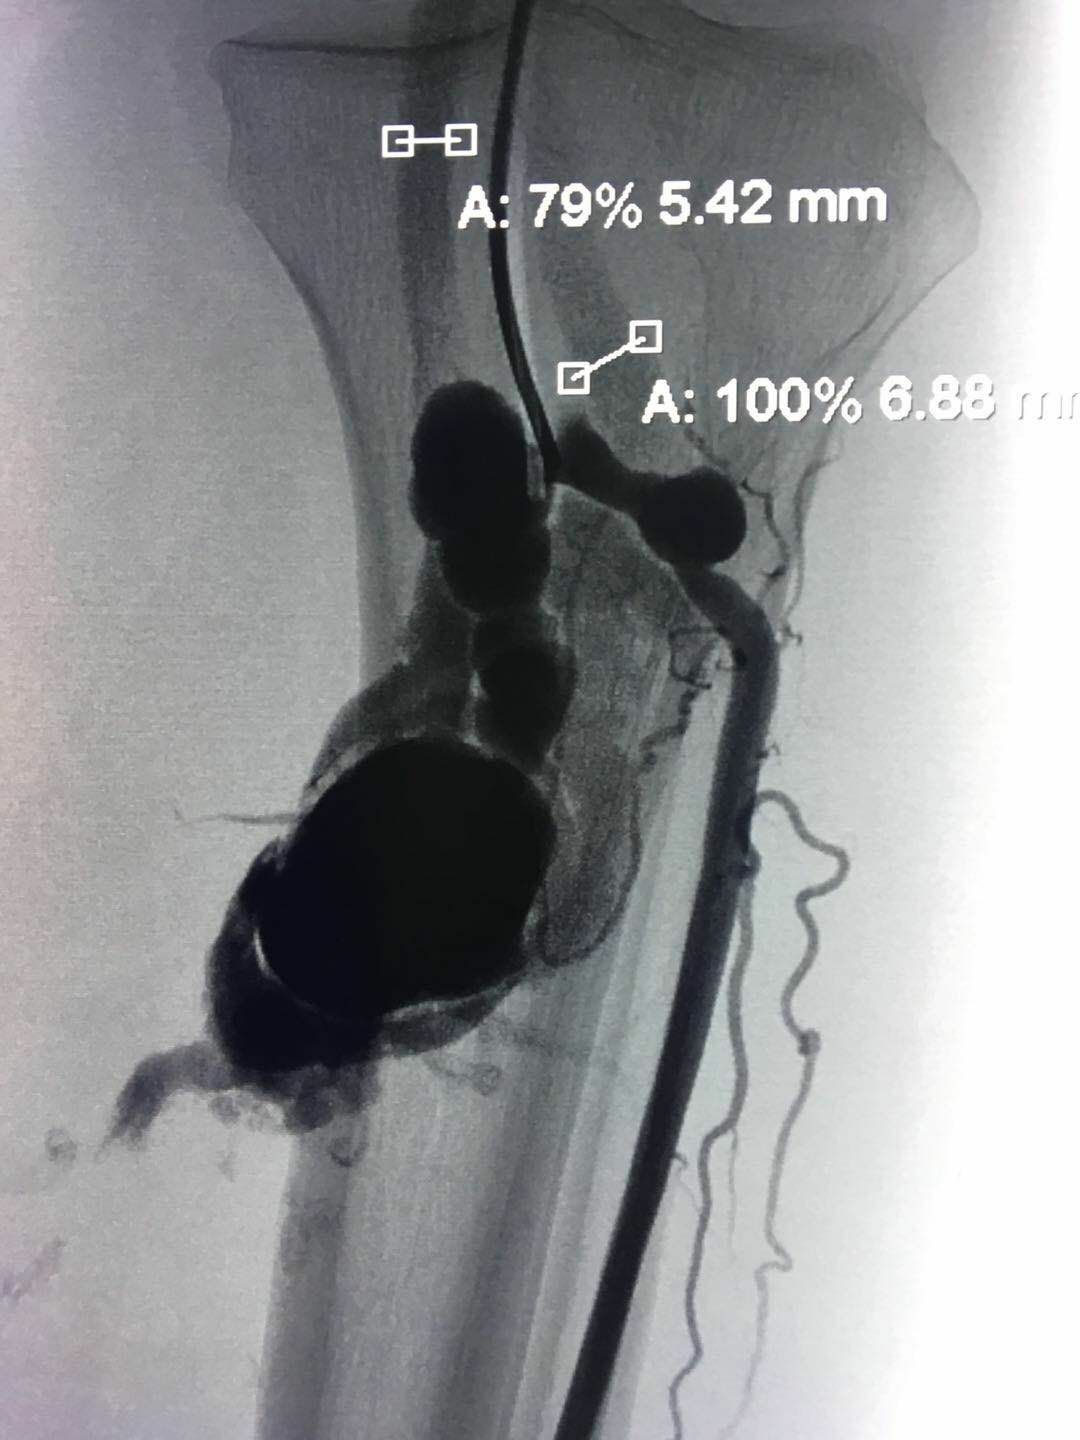

圖2:引流靜脈粗大